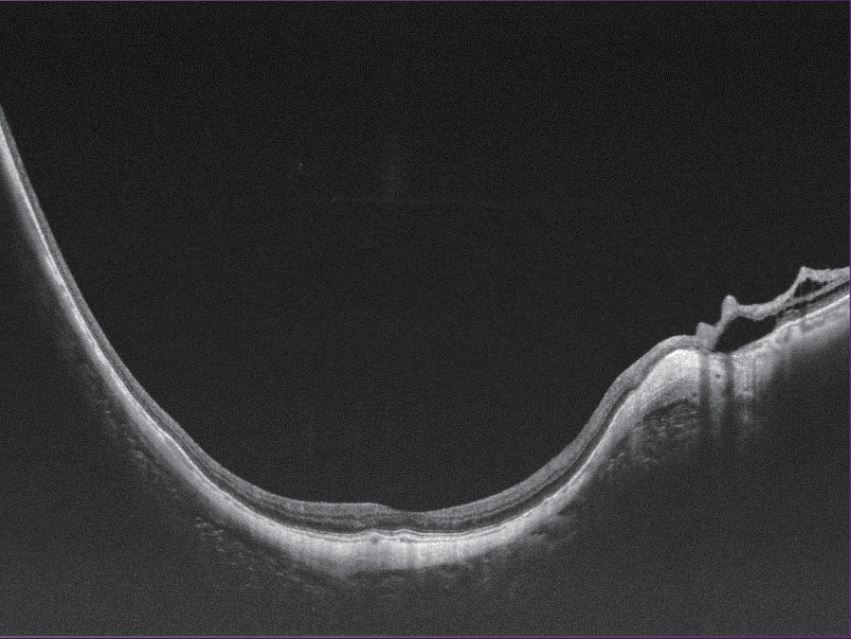

Full Range Retina OCT

- Van achterste glasvocht tot choroidea-sclera

- 17 mm tot 12 mm netvliesscan

- Automatische laagdetectie, segmentatie en meting van elke laag van het netvlies en choroïd